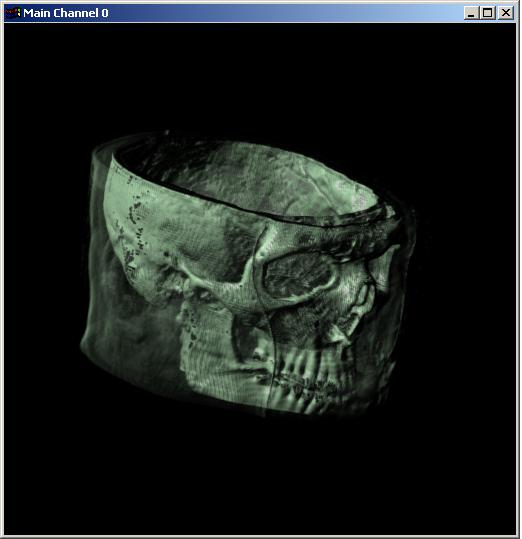

Visible human male CT data

Skin only

Data Resolution : 256x256x128

The following 12

images was generated by PC which has NVIDIA's GeForce3 GPU graphics card. The

hardware accelerated rendering techniques are used to make the following images.

To use the GeForce3 hardware, we have to use the OpenGL extensions like

GL_NV_texture_shader2, GL_NV_register_combiners, GL_EXT_texture3D,

GL_EXT_paletted_texture, GL_ARB_multitexture and so on. Since the GeForce3 card

allows the 3D texture shading, the image quality is better than the pixel of

frame buffer based shading in showing two materials at the same time.